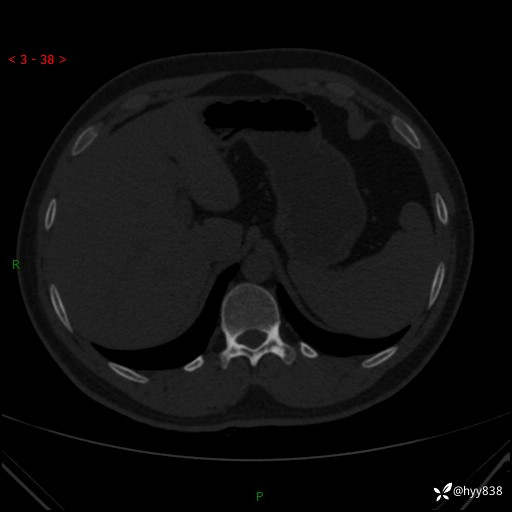

患者性别:男

患者年龄:28岁

简要病史:右肾肿瘤术后,常规复查

辅助检查:CT

临床诊断:右肾肿瘤术后

腹部CT+颅脑CT平扫